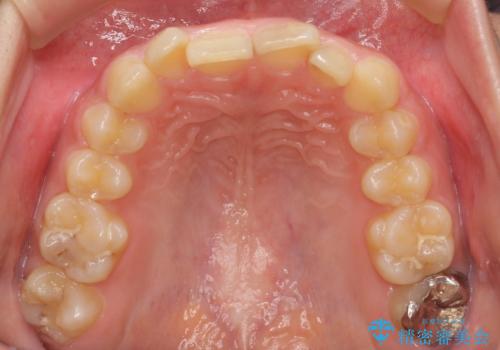

前歯のがたつき 過蓋咬合

- 上の小臼歯を2本抜歯して矯正を行いました。

一般的には、抜歯を行うと前歯はより内側に倒れこむため、初めから内側に倒れ込んでいると矯正の難易度は上がります。

今回は上の前歯が内側に傾いている症状があり(Angle Ⅱ級2類)、その修正に時間がかかっています。

一見同じような歯並びに見えても、前歯の角度や、奥歯の上下の噛み合わせによって難易度には差があります。